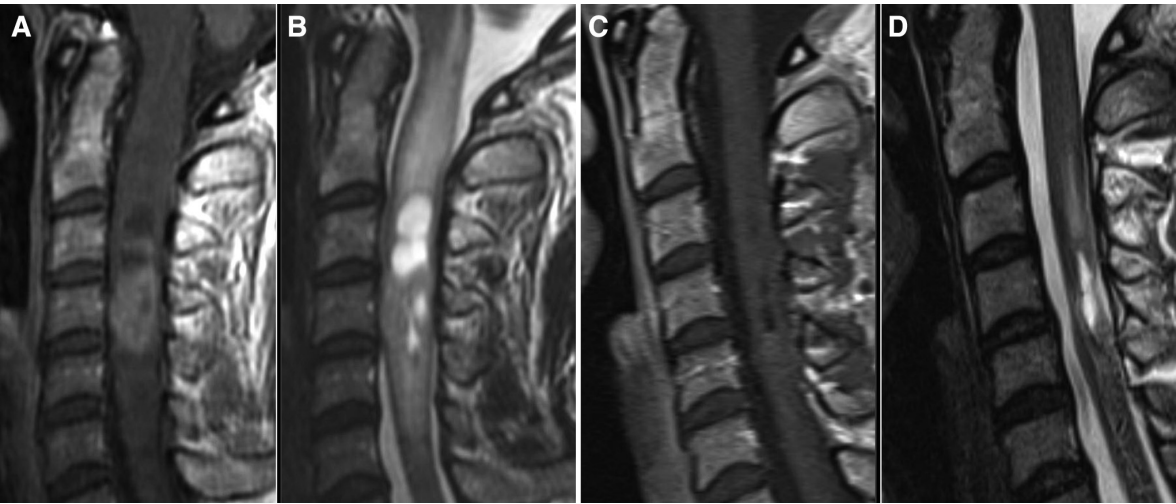

INC国际神经外科顾问团成员教授、国际神经外科联合会WFNS立体定向与功能神经外科主席、德国汉诺威医学院MHH神经外科主席兼教授Joachim K. Krauss在其论文《Surgical Treatment of Spinal Ependymomas: Experience in 49 Patients》中报告了在18年中49例患者的治疗结果,回顾性分析患者的临床及影像学资料。

在该研究中,手术患者平均年龄46.4岁。女性29例(59%),男性20例(41%)。总切除率72%。肿瘤累及颈髓14例(29%),脊髓圆锥8例(16%),胸髓7例(14%),颈腰段或胸腰椎交界处10例(20%)。术后放疗6例。对39例患者进行了长期随访(平均50.7个月)。术前麦考密克评分高与术后临床恶化的相关。在长期随访中,51%的患者的临床状况与术前相同,21%的患者恶化,28%的患者好转。在组织学方面,我们没有发现无进展生存率的差异。4例肿瘤在平均21个月无进展生存后复发。

较后,Krauss教授得出结论,室管膜瘤是一种少见的脑室肿瘤,发生于成人的髓内。较好的结果是在疾病的早期,当神经症状较轻时进行手术。术后即刻,许多患者的神经系统状况可能恶化,但术前临床状况良好的患者可期望几个月后症状好转至术前状态。脊髓室管膜瘤行全切除术是优选治疗方法。较重要的临床预后评估指标是术前神经功能。术后放疗的作用有待进一步阐明。